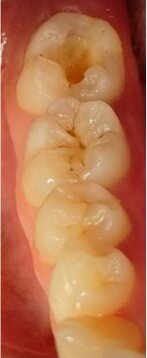

Once the copy of the occlusal face had been obtained, the lesion of tooth #47 was opened with a small round diamond bur at high speed and under abundant water irrigation. The resulting Class I cavity (Fig. 4) was restored with EQUIA Forte HT (Shade A2). Once the relative isolation with cotton rolls had been done, a very thin layer of GC Cocoa Butter (GC Europe) was applied to the adjacent teeth and areas where the glass hybrid was not to adhere. Owing to the good handling properties and the handy capsule format of EQUIA Forte HT, the material can be homogeneously mixed and injected into the cavity fast and easily. By applying the content of a single capsule, we managed to cover the cavity completely, and then we placed the stamp (Fig. 5), previously obtained with the low-viscosity resin, and pressed firmly on top of the tooth and restorative material. Excess was removed with the help of a spatula and probe during the rubbery phase of the glass hybrid. The stamp was removed, revealing the beautifully reproduced occlusal anatomy (Fig. 6). No separating agent, such as glycerine or PTFE tape, was required since the stamp does not stick to the glass hybrid material. When a resinous stamp is used, light-polymerising a resin composite restoration with the stamp in situ might cause issues—owing to light attenuation as well as co-polymerisation of the stamp with the restoration itself.

Fig. 6: After removal of the stamp, the nicely shaped occlusal anatomy could immediately be seen.

To finish the restoration, any excess material that remained was removed with a probe and a small flame-shaped diamond bur was only briefly used on the mesiolingual cusp to make a small occlusal adjustment. EQUIA Forte Coat facilitates the final steps of the restoration, as no polishing procedures are required. The field was again isolated with cotton rolls, and a thin layer of EQUIA Forte Coat (Fig. 7) was applied and light-polymerised for 20 seconds, leaving a smooth, shiny surface (Fig. 8). The coat is on average 35–40 µm thick and did not interfere with the occlusion.